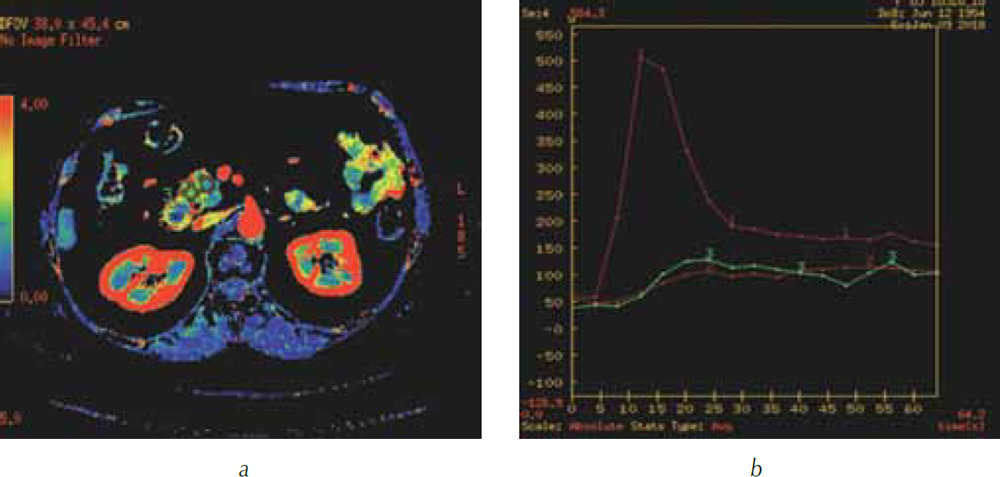

Выполнение КТ-перфузии поджелудочной железы с построением перфузионных карт позволило четко визуализировать опухоль в головке поджелудочной железы, оценить ее границы и размеры, выявить распространение на перешеек поджелудочной железы (рис. 4), измерить показатели перфузии в опухоли и неизмененной паренхиме головки (рис. 5).

Рис. 4. КТ-перфузия поджелудочной железы: а — перфузионная карта скорости кровотока (BF). Опухоль в головке поджелудочной железы определяется в виде участка синего и зеленого цветов (короткая стрелка), четко видны границы опухоли с неизмененной паренхимой, имеющей красный цвет (длинная стрелка); b — трехмерная реформация в аксиальной проекции. Панкреатическая фаза. Головка поджелудочной железы (стрелка) равномерно накапливает контрастный препарат, опухоль не видна; c — перфузионная карта скорости кровотока (BF). Размеры опухоли составили 26,6 × 20,3 мм

Рис. 5. КТ-перфузия поджелудочной железы: а — перфузионная карта скорости кровотока (BF). В опухоли (участок синего цвета) установлен ROI2, в не вовлеченной в опухолевый процесс ткани головки (участок красного цвета) ROI3; b — график зависимости «время – плотность». Красным цветом (№ 1) обозначена зависимость показателей «время – плотность» в брюшной аорте, красным цветом (№ 2) в опухоли, зеленым цветом (№ 3) в не вовлеченной в опухолевый процесс ткани поджелудочной железы. Показатели перфузии в опухоли составили: BF — 37,5 мл/100 г/мин, BV — 3,3 мл/100 г, MTT — 5,5 с; в неизмененной паренхиме головки: BF — 117 мл/100 г/мин, BV — 10,6 мл/100 г, MTT — 8 с